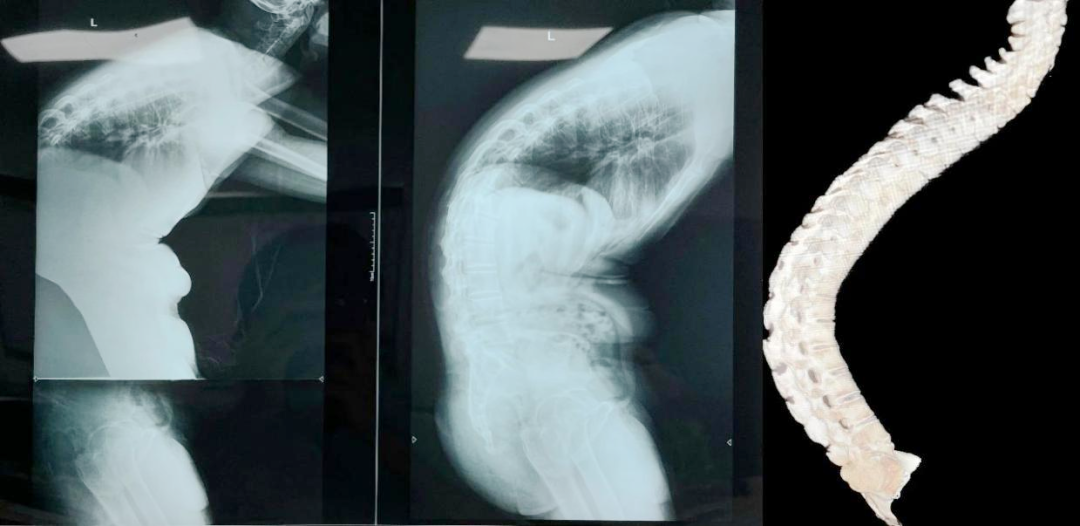

4.高难度畸形矫形大师:面对强直性脊柱炎严重后凸(术前Cobb角高达70°)、重度脊柱侧弯等复杂畸形,团队展现出非凡的规划与执行能力。他们术前周密设计,综合考虑患者直立、平视、端坐、平躺等全方位功能需求,精确计算截骨位置与角度,制定个性化方案。成功实施多例高难度截骨矫形术(如腰2/3、腰1/2、腰1/胸12、胸11/12截骨),结合椎管扩大成形、神经根管减压及钉棒内固定,实现了“小切口、大矫形”的完美效果,让佝偻的身躯重新挺立。

▲术前:术前正侧位,脊柱后凸CObb角70°